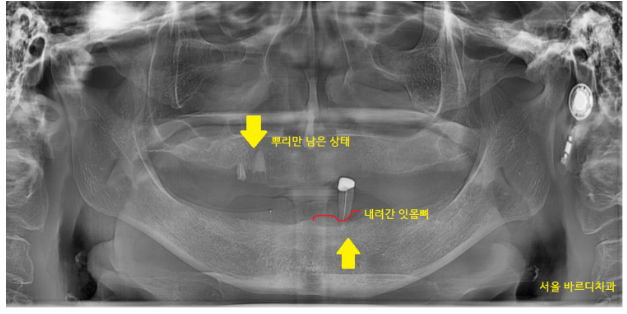

틀니를 기존에 쓰시던 분이라

뼈가 많이 퇴축된 것이 보이네요~

아래 치아 같은 경우 뼈 자체가 얇았습니다.

위에 치아는 상대적으로 입천장이 있어

틀니가 빠지거나 큰 불편감이 없지만

아래 치아는 혀가 있어서

틀니가 잘 빠질 수 있습니다.

뼈도 얇아 틀니를 만들게 되어도

잇몸에 눌려 아프거나 불편하실 수 있을듯 하였습니다.

이대로 완전 틀니를 만들어 드리면

뼈는 더 퇴축되어

나중에는 임플란트를 하고 싶어도 못할 수 있는데요.

지금이 수술할 수 있는 마지막 기회일지 몰라

하악은 임플란트를 부분적으로 심고

그 위에 틀니를 올리자 설명드렸습니다.